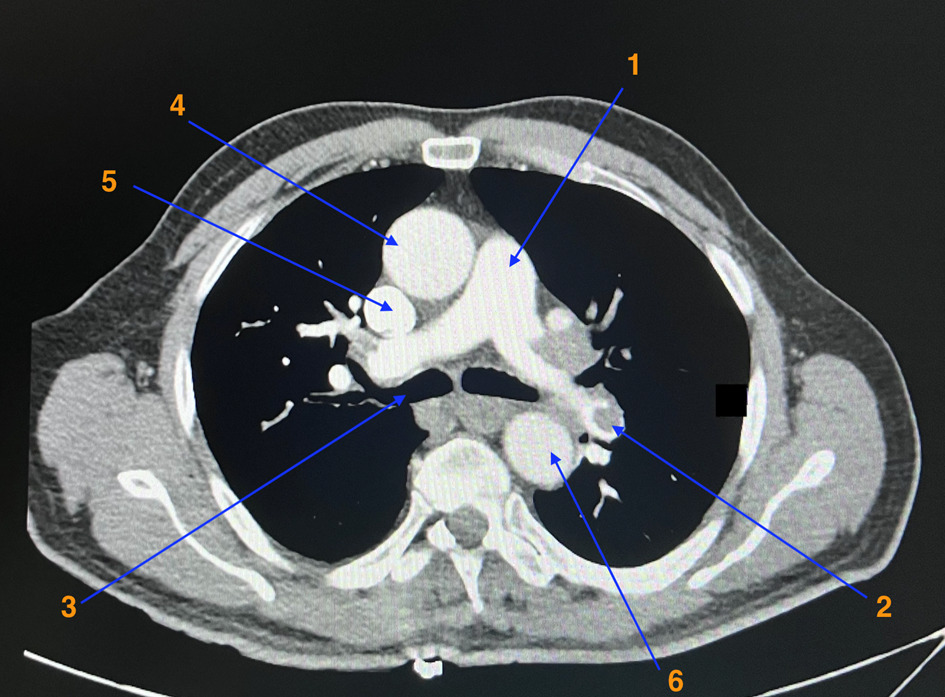

Oui, douleur évocatrice, antécédent de TVP, dyspnée.

Toujours y penser mais la douleur n’est pas typique, la tension est symétrique ainsi que les pouls périphériques n’expliqueraient pas la dyspnée.